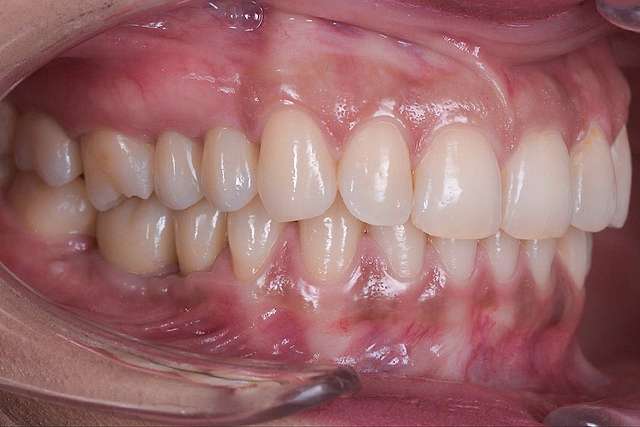

For optimal esthetic results, the final design must always be the refference for the surgery. This design together with the CBCT of the patient are compiled to find the ideal position of the dental implants.

When implant therapy is performed with guided surgery, the surgery itself is simpler, and trauma is reduced especially for the soft-tissues. Overall we can achieve faster healing and better post-op comfort.